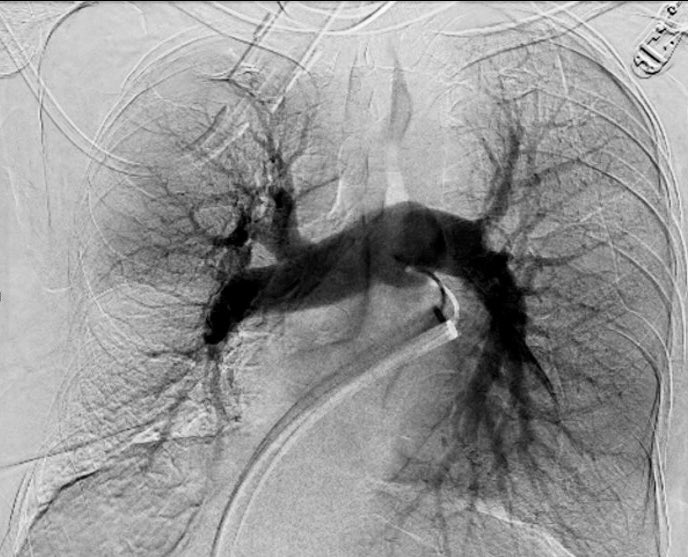

TEP, sistemas de trombectomia, equipos PERT entrenados, Guias de navegación endovascular. Resultados inmediatos. 🇨🇱 Temuco 💪 @HHHATEMUCO @RadiologiaChile @SIDISoc @colmedchile @DrCOlivares @InariMedical @teptips @rduranmendez

Tromboembolismo de arteria pulmonar o TEP. 3era causa de muerte cardiovascular. Araucania con terapia de 1er mundo. Guias de manejo actualizadas. Equipos PERT. Caso de la semana pasada 👌 Mejorando la salud de nuestra población con lo mejor que tiene la medicina, orgulloso

Caso trombectomía aspirativa en #TEP en ⁦@HHHATEMUCO#PE #FLAME #Irad@SIDISoc⁩ ⁦⁦@RadiologiaChile⁩ ⁦@sochimioficial⁩ ⁦@sochimu⁩ ⁦@Sochicaroficial⁩ ⁦⁦@SOCHIVAS_Chile⁩ ⁦@InariMedical#Flowtriever